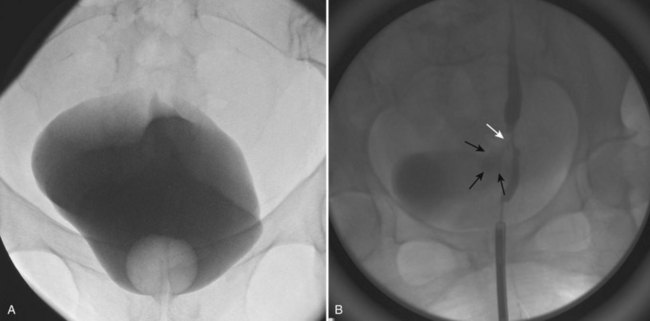

A cystogram and/or voiding cystourethrogram (VCUG) and an upper tract study should be performed in patients being evaluated for a VVF. The cystogram may objectively determine the presence and location of the fistula. Upon filling of the bladder, contrast often begins to opacify the vagina, almost immediately confirming the presence of a VVF. VVF are often best seen in the lateral projection (Fig. 77–7) in which the bladder and vagina are not superimposed. Often, the actual VVF tract may be visible in the lateral projection (Fig. 77–8). However, voiding images may be necessary in some patients with small fistulae, to demonstrate the VVF. The slight increase in intravesical pressure that accompanies micturition is usually adequate to demonstrate even very small fistulae. Importantly, a cystogram that fails to demonstrate a suspected VVF, but lacks voiding images or postvoid images, should be considered nondiagnostic. During voiding, care should be taken to exclude vaginal voiding or reflux of contrast from the introital region cephalad into the vagina, which would produce a falsely positive image. An involuntary bladder contraction can be provoked with rapid filling during cystography, and if the intravesical pressure rises sufficiently, this may also be sufficient to demonstrate a VVF when the filling images of the cystogram failed to demonstrate it. In some instances, a cystogram can also make an assessment of bladder capacity (important in the setting of prior radiotherapy), cystocele, bladder neck competence, and vesicoureteral reflux, any of which may have an impact on operative repair.

Figure 77–7 Cystogram demonstrating a vesicovaginal fistula (VVF). A, Lateral image demonstrates a posthysterectomy VVF. B, Anteroposterior view. The contrast agent is seen opacifying and outlining the vagina superimposed on the bladder.